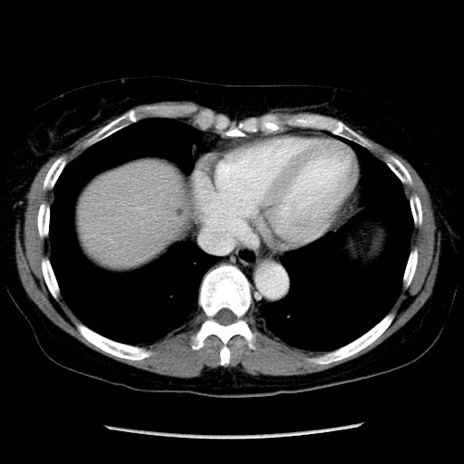

症例6(横断像)

【症例】50歳代女性

【主訴】下腹部痛

【現病歴】本日朝より下痢2回あり。 昼食を食べた後、嘔吐3回、下腹部痛認め、症状軽快せず、当院救急搬送。

【既往歴】卵巣癌術後(8年前に当院で卵巣摘出)

【身体所見】 意識清明、腹部:平坦、腸蠕動音→、やや硬、下腹部自発痛・圧痛あり、反跳痛あり、筋性防御なし。

【データ】WBC 16000、CRP 0.01